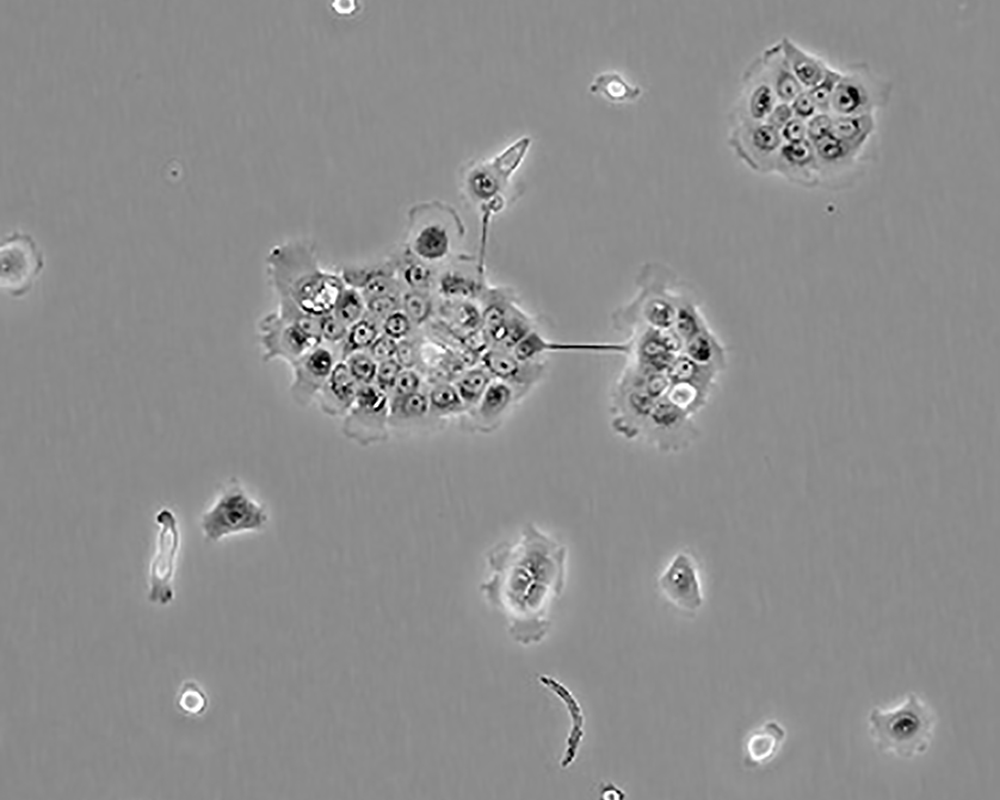

BxPC-3(BxPC3)

產(chǎn)品名稱 BxPC-3(BxPC3)

中文名稱 人原位胰腺腺癌細(xì)胞

組織來源 胰腺導(dǎo)管腺癌;女性

生長特性 adherent

形態(tài)特征 epithelial

細(xì)胞描述 The cells do not express the cystic fibrosis transmembrane conductance regulator(CFTR). A CFTR positive pancreatic line, Capan-1 is available.